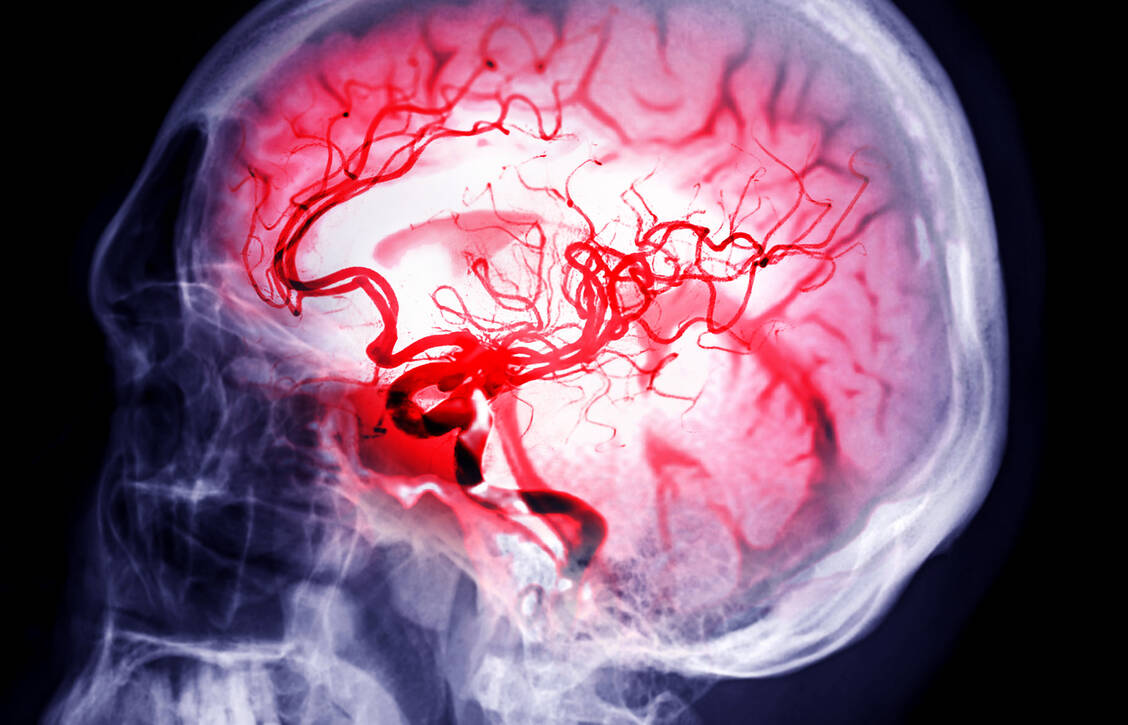

Der Zusammenhang zwischen einer gesunden Mundflora und dem Risiko für ischämische Ereignisse ist bereits länger bekannt. Eine neue Analyse der Atherosclerosis Risk in Communities-(ARIC)-Studie zeigt nun...weiterlesen »